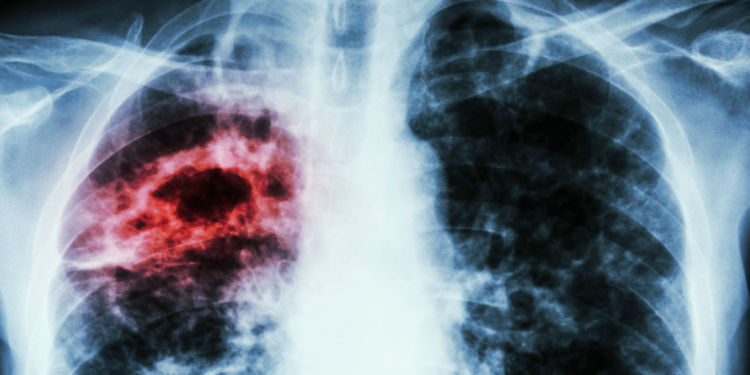

Chaque jour, près de 100 nouvelles personnes contractent la tuberculose au Maroc, et la maladie entraîne la mort de 9 individus. Malgré les efforts en cours, la baisse de l’incidence de la tuberculose progresse à un rythme très lent. Les zones les plus touchées sont les quartiers densément peuplés et les régions défavorisées, où les conditions de vie difficiles exacerbent la propagation de la maladie.

Le Maroc continue de faire face à un défi majeur avec la tuberculose. Cette année-là, 35 000 nouveaux cas ou rechutes ont été enregistrés, soit un taux d’incidence de 94 pour 100 000 habitants, avec un total de 3 300 décès.

Le médecin et chercheur Tayeb Hamdi souligne la gravité de la situation, indiquant qu’un patient sur dix atteint de tuberculose décède, ce ratio atteignant un sur cinq chez les personnes co-infectées par le VIH. Il exprime également son inquiétude face à la lenteur de la baisse de l’incidence, qui n’a diminué que de 1 % par an entre 2015 et 2021, loin de l’objectif d’éradication pour 2030.

La maladie touche principalement les hommes (59 %) par rapport aux femmes (41 %), et affecte surtout les jeunes adultes de 25 à 34 ans, une tranche d’âge cruciale pour l’économie. Les zones les plus touchées sont les quartiers surpeuplés et les régions périurbaines, notamment Tanger-Tétouan-Al Hoceima, Rabat-Salé-Kénitra, et Casablanca-Settat.